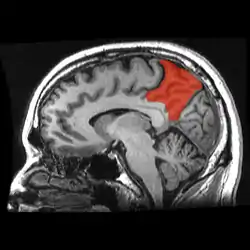

Precuneus

The precuneus is the portion of the superior parietal lobule on the medial surface of each brain hemisphere. It is located in front of the cuneus (the upper portion of the occipital lobe). The precuneus is bounded in front by the marginal branch of the cingulate sulcus, at the rear by the parietooccipital sulcus, and underneath by the subparietal sulcus. It is involved with episodic memory, visuospatial processing, reflections upon self, and aspects of consciousness.

![]() Sagittal MRI slice with the precuneus shown in red. | |